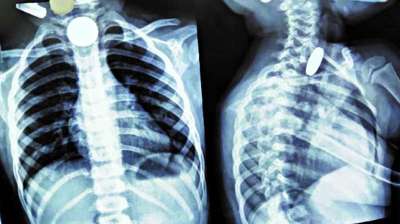

खिलौना नहीं सिक्का था! बच्चे ने निगले 5-10 रुपये के सिक्के, डॉक्टरों ने ऑपरेशन कर निकाले

24 Jul, 2025 04:09 PM IST | BRIGHTNEWS.IN

दिल्ली : दिल्ली के एक सरकारी अस्पताल के डॉक्टरों ने 12 वर्षीय बच्चे की जान बचाई है। बच्चे ने पांच और दस रुपये के तीन सिक्के निगल लिए थे। सिक्के...